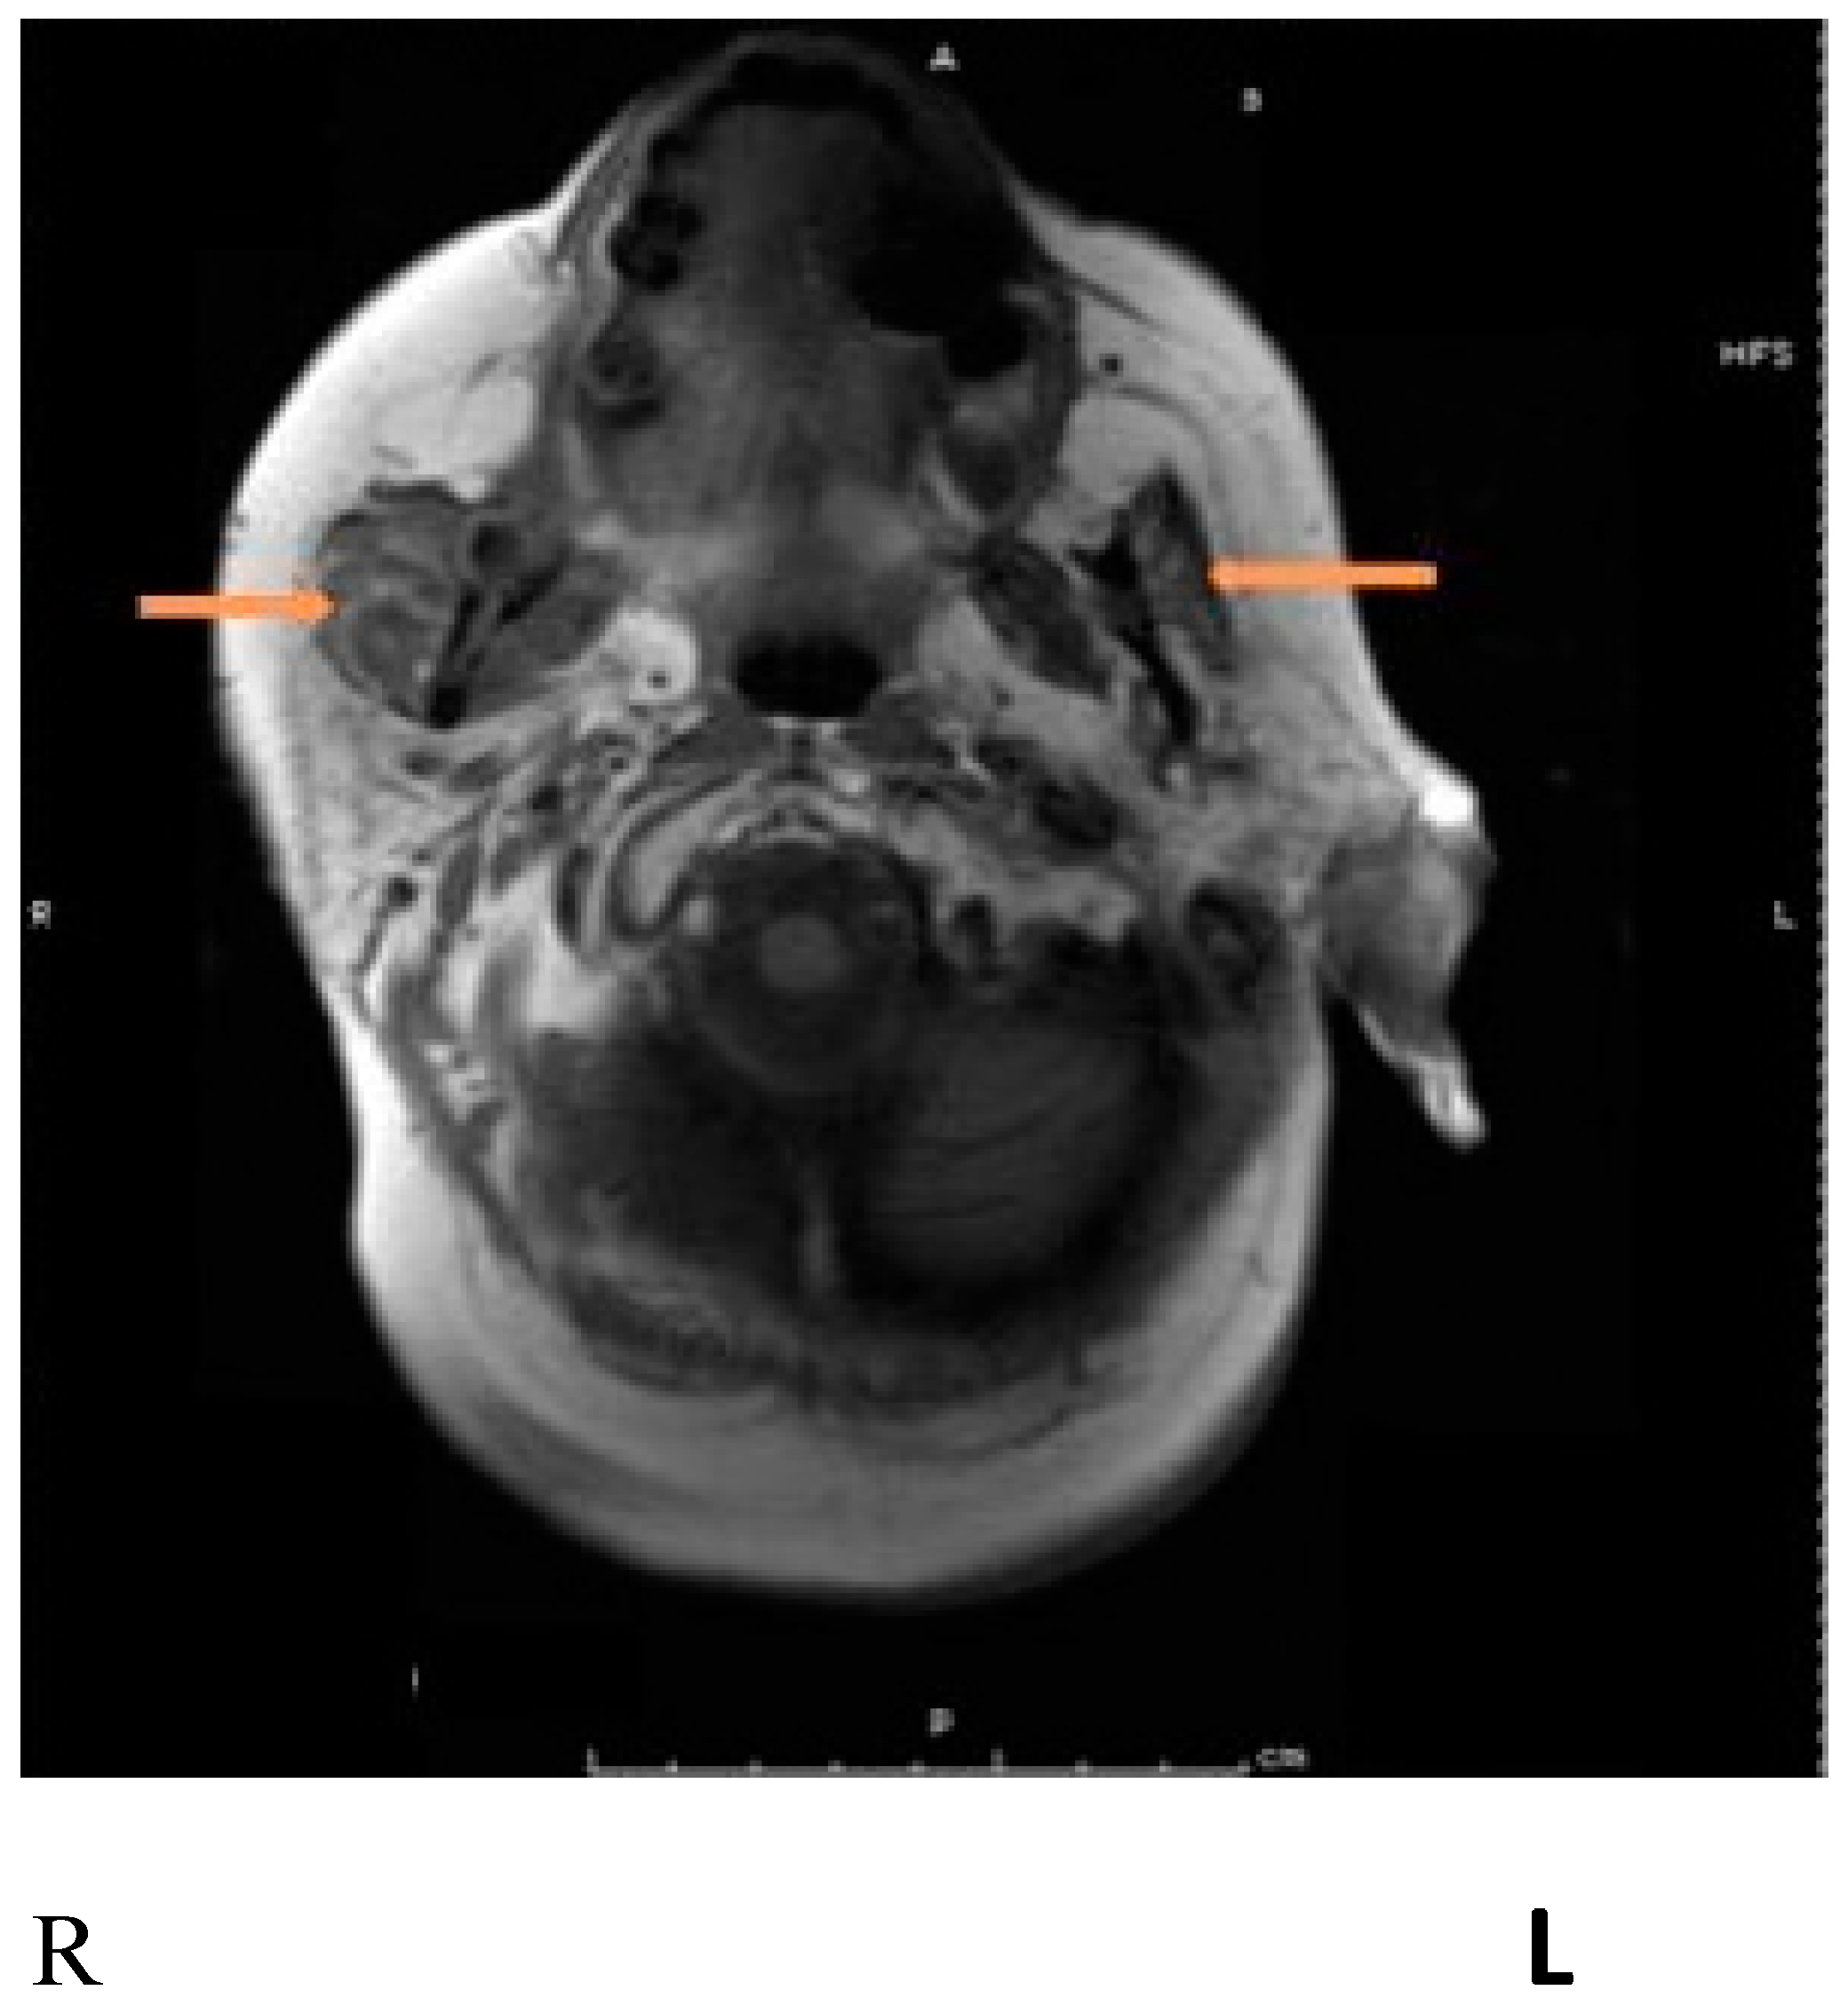

- Mueller, J.; Langbein, T.; Mishra, A.; Baum, R.P. Safety of High-Dose Botulinum Toxin Injections for Parotid and Submandibular Gland Radioprotection. Toxins 2022, 14, 64. [Google Scholar] [CrossRef]

| Mueller et al., 2022 [70] | Pro | 10 | Prostate cancer Post Ac-PSMA therapy | face | IncoA, 6 injections, 30 u per injection point | Those injected by BoNT showed a mean of 29% gland destruction after two cycles of Ac-PSMA treatment compared 60–70% seen in those who did not receive BoNT injection |